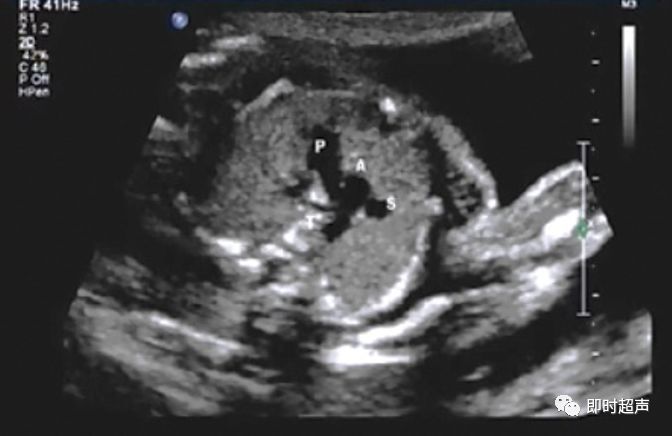

探到胎儿四腔心后,探头稍向胎儿头侧偏移即可显示三血管-气管切面,正常三血管-气管平面从左到右依次显示:肺动脉、主动脉弓、气管、上腔静脉。

胎儿正常三血管-气管平面示意图

胎儿三血管气管切面

三血管-气管切面的观察内容

- 从左到右依次是肺动脉、主动脉弓和上腔静脉

- 内径从左到右依次递减

- 主动脉弓位于气管的左侧

- 肺动脉和主动脉弓血流都流向脊柱,呈后向血流

- 肺动脉经动脉导管与主动脉弓共同汇入降主动脉